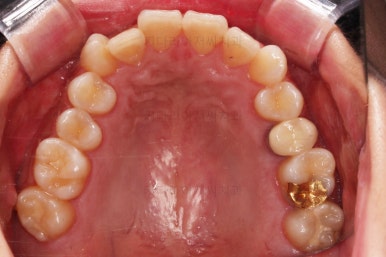

1. 초진

연산동교정치과 초진 시 입안의 모습입니다.

얼핏 앞에서 봤을 때 치열이 나쁘지 않아 보이는데요.

대신 자세히 살펴보면 윗니 양쪽 송곳니가 덧니처럼 볼록 튀어나와 있고요.

아랫니 어금니가 하나 없어서 주위 치아들이 해당 위치로 쓰러진 상태였습니다.

그리고 양쪽의 교합이 톱니바퀴처럼 맞물려 있는 것 같지만 톱니바퀴가 한 칸씩 밀려서 맞물려 있는 부정교합이 있는 상태였습니다.

이번 환자분은 다행히 해당 부분에 사랑니까지 있었고 상태가 나쁘지 않았기 때문에 사랑니까지 앞으로 끌고 당겨와서 사용하기로 했습니다.

임플란트 없이 마무리 하겠다는 뜻이죠.